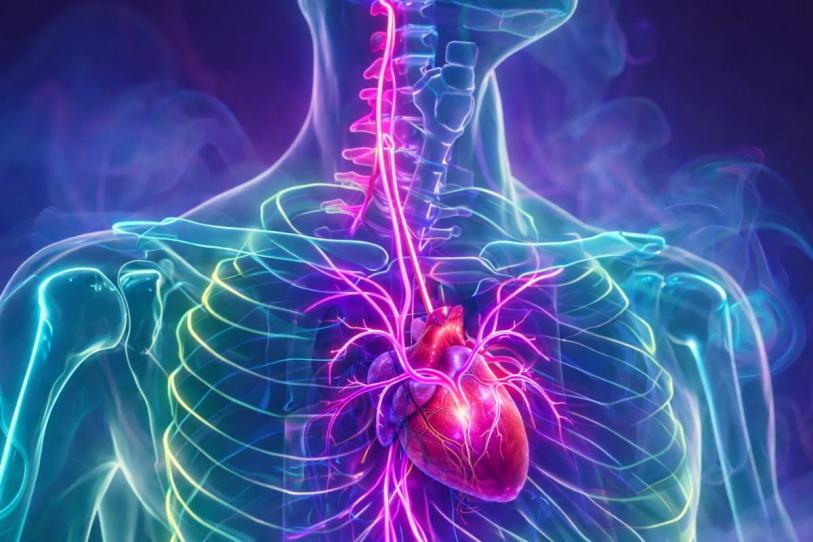

Ciudad de México, Enero 5.- Cuando se piensa en la salud del corazón, casi siempre se habla de arterias, colesterol o presión arterial. Sin embargo, un estudio reciente ha puesto el foco en un actor mucho menos visible: un nervio que recorre el cuello y conecta directamente con el corazón.

El nervio vago es uno de los nervios más largos e importantes del cuerpo humano. Se origina en el cerebro y desciende por el cuello hasta llegar a órganos vitales como el corazón, los pulmones y el sistema digestivo.

Su función principal es servir como una vía de comunicación constante entre el cerebro y el resto del cuerpo, regulando procesos automáticos que no controlamos de manera consciente.

Entre esas funciones se encuentran la frecuencia cardiaca, la presión arterial y la respuesta del organismo frente al estrés.

En el caso del corazón, el nervio vago actúa como un modulador natural del ritmo cardiaco. Una actividad vagal adecuada suele asociarse con un corazón más eficiente y adaptable.